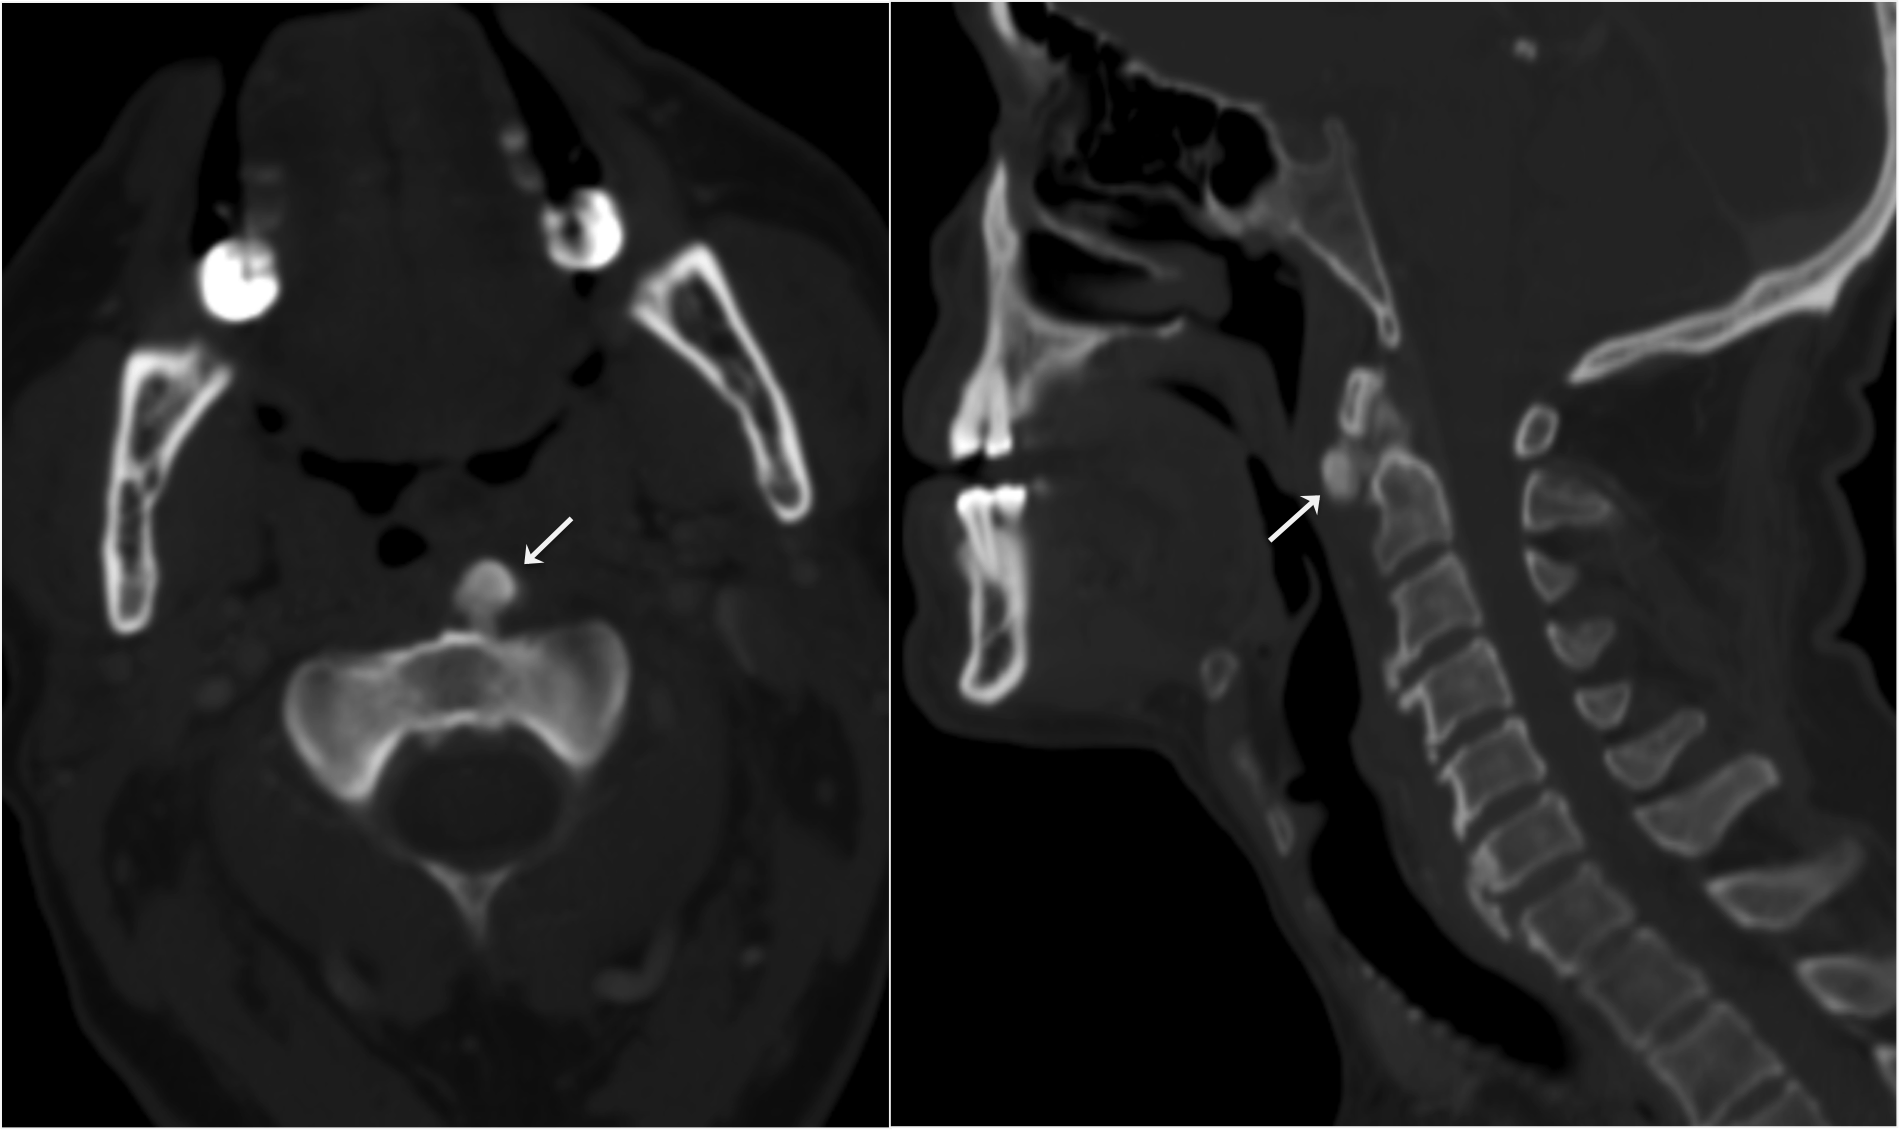

Acute calcific tendinitis of the longus colli (CTCL) is a rare, self-limited and probably under diagnosed cause of acute neck pain in which the radiologist can make a definitive diagnosis. It commonly mimics potentially serious conditions affecting the retropharyngeal space. We report a case of a 63-year old male presenting in the emergency department with acute throat pain. Imaging findings were diagnostic of CTCL. A brief review of the literature is provided.